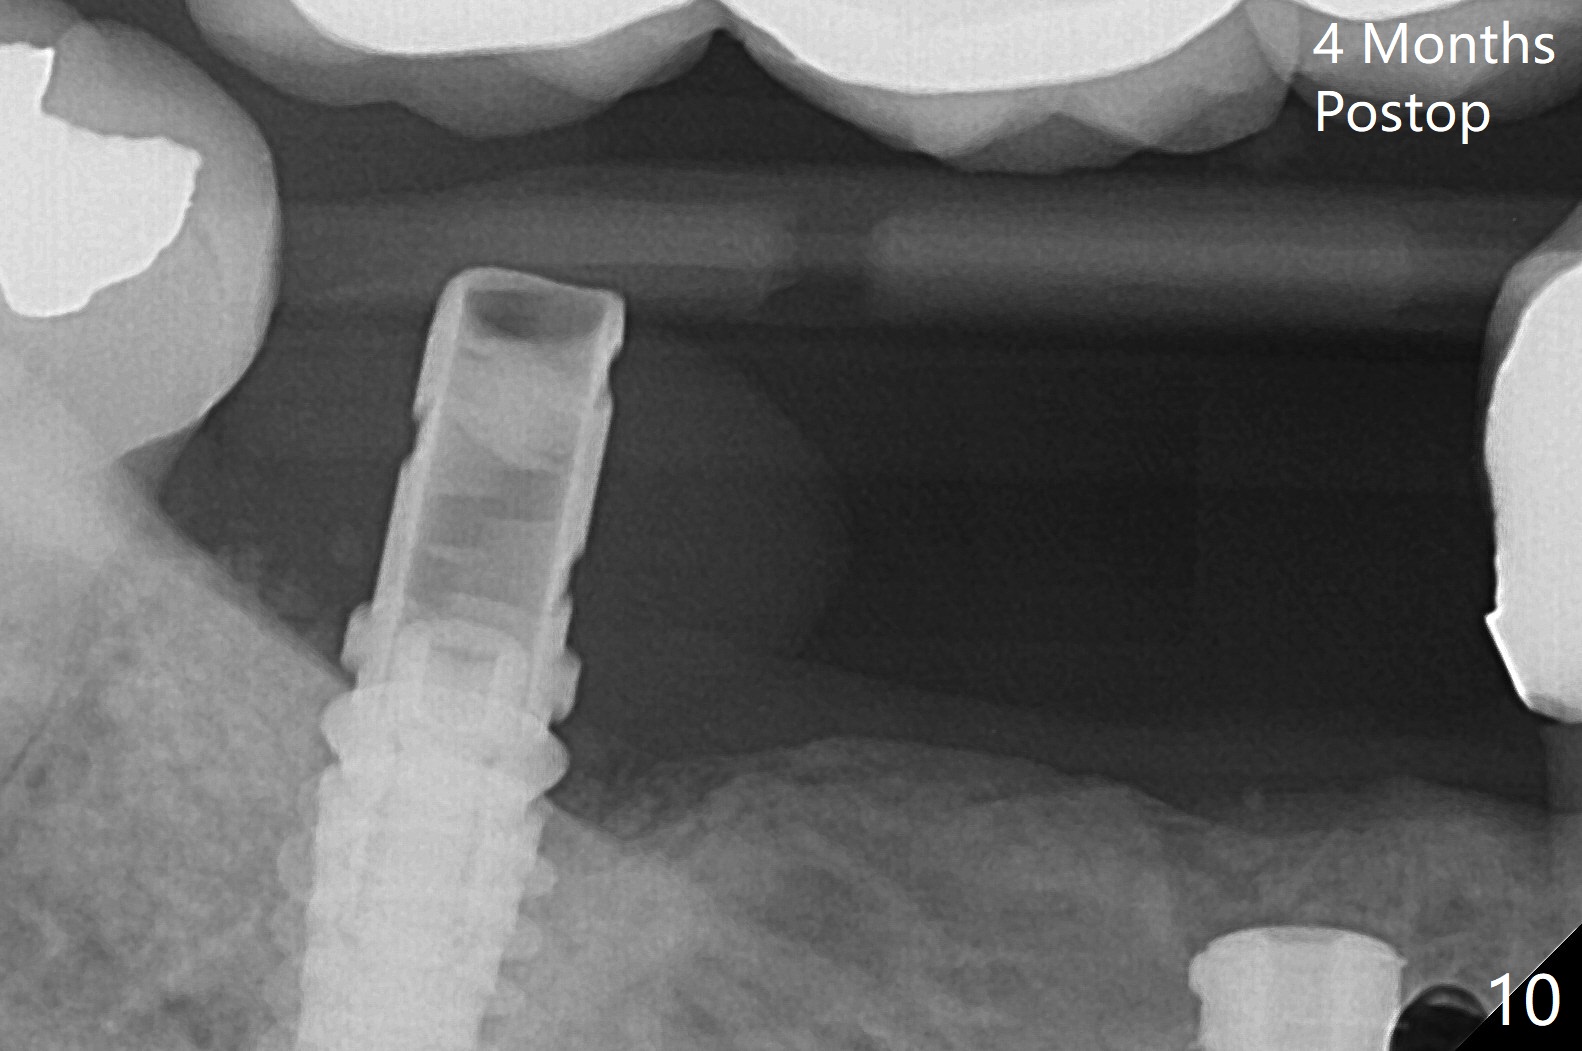

The extraction socket of #31 has a thin septum (Fig.2), which is removed partially with 12 mm bone trimmer (Fig.3). After placement of a 5x9 mm FC implant (~40 Ncm) and 6 mm bone profile drill, a 5.5x4(2) mm abutment is incompletely seated (Fig.5 <) and later is changed to a 4.5x1 mm temporary abutment (Fig.6, 8 T). The latter is used to fabricate a provisional, which in turn supports the distal papilla (Fig.8 *). The gingiva is slightly erythematous immediately post periodontal dressing removal (3 weeks postop, Fig.9). Take CT to confirm whether the cortical drill helps keep the #29 implant lingual. Use a profile drill at #29 if crestal bone loss is not obvious. There is bone coronal to #29 implant 4 months postop (Fig.10). Upon incision, the ridge is rounded (Fig.10'), but the implant appears to be buccally placed (Fig.10'' (post high speed handpiece and 5.5 mm profile drill)). The latter is confirmed by CT (Fig.12, as compared to design (Fig.11)). In spite of use of cortical drill coronally, the implant is still deviated buccally due to contrasting deferential bone density linguobuccally (Fig.13). By comparison, there is no such bone density differential involving an immediate implant at #31; the implant is placed in the socket without contacting the buccal or lingual cortices (Fig.14). The final implant is the same as expected (Fig.15). To avoid implant deviation in the lower premolar region, leave the root in place until osteotomy is finished. Five months postop, the temporary and healing abutments at #31 and 29 change to pair ones (Fig.16). Since there is limited clearance from the crestal bone, smaller abutments are used with the apparently same degree of seating (Fig.17). The abutments are prepared due to the mesial (#31) and buccal (29) tilt before impression.